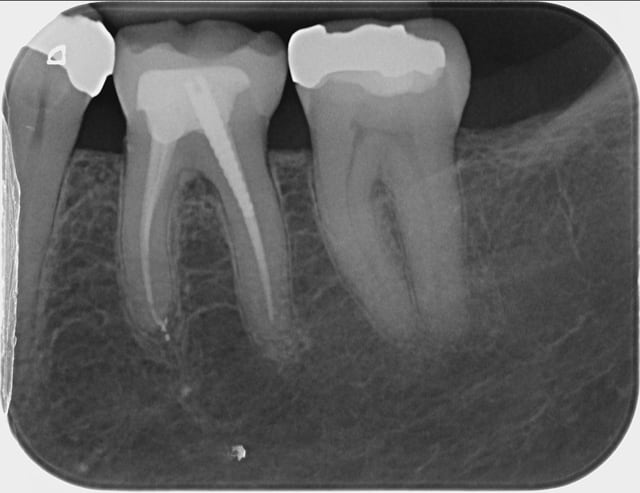

Capture d  cran 2015 03 12 12.28 - Eugenol